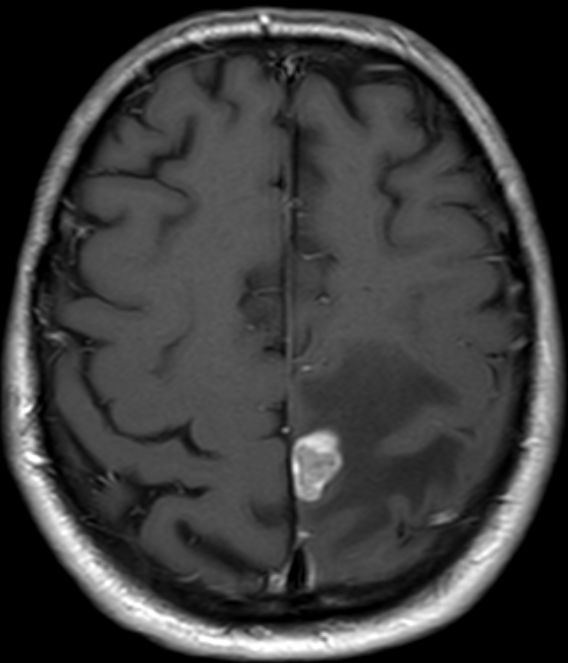

| Hirnmetastasen | OS 6,7 Monate nach Ganzhirnbestrahlung oder oder stereotaktischer Bestrahlung

![]() | |||